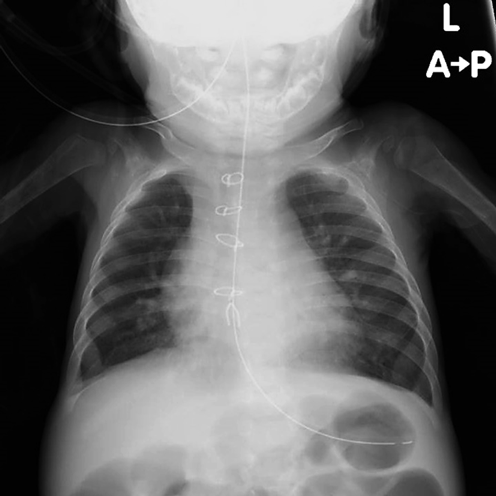

肥大型心筋症を合併した心房中隔欠損症に対して開窓付閉鎖術が奏功した1例Fenestrated Closure of an Atrial Septal Defect for Left Ventricular Diastolic Dysfunction in an Early Infant with Hypertrophic Cardiomyopathy